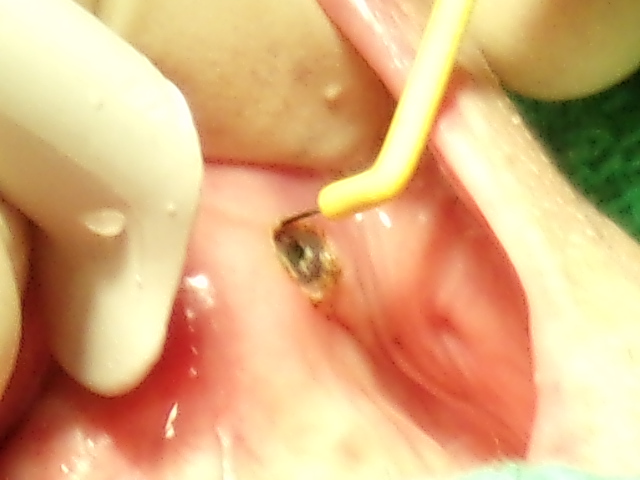

歯科治療の一例

提携 歯科技工所への発注 口腔外科疾患に対する処置

歯科口腔外科用器具による処置 歯肉処置の例

口腔外科に準じた処置 インプラントの埋入手術(上顎)